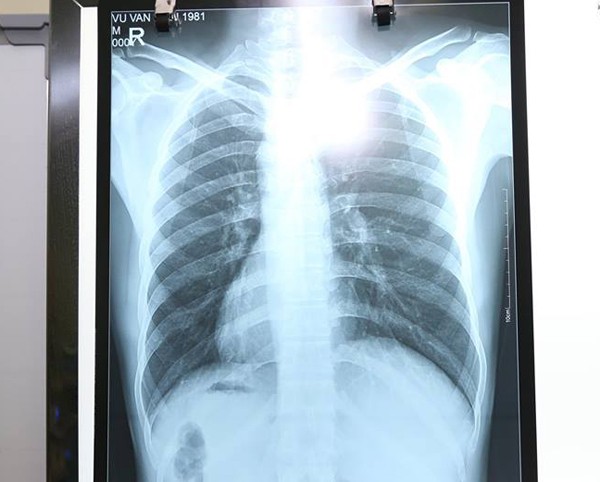

Tuy nhiên, điều khiến các bác sĩ kinh ngạc là tim cùng các phủ tạng khác trong lồng ngực và bụng của bệnh nhân đều ở vị trí ngược so với bình thường, tim và dạ dày đều ở bên phải còn gan, ruột thừa nằm ở bên trái.

Nội tạng của anh H. đảo ngược so với người bình thường.